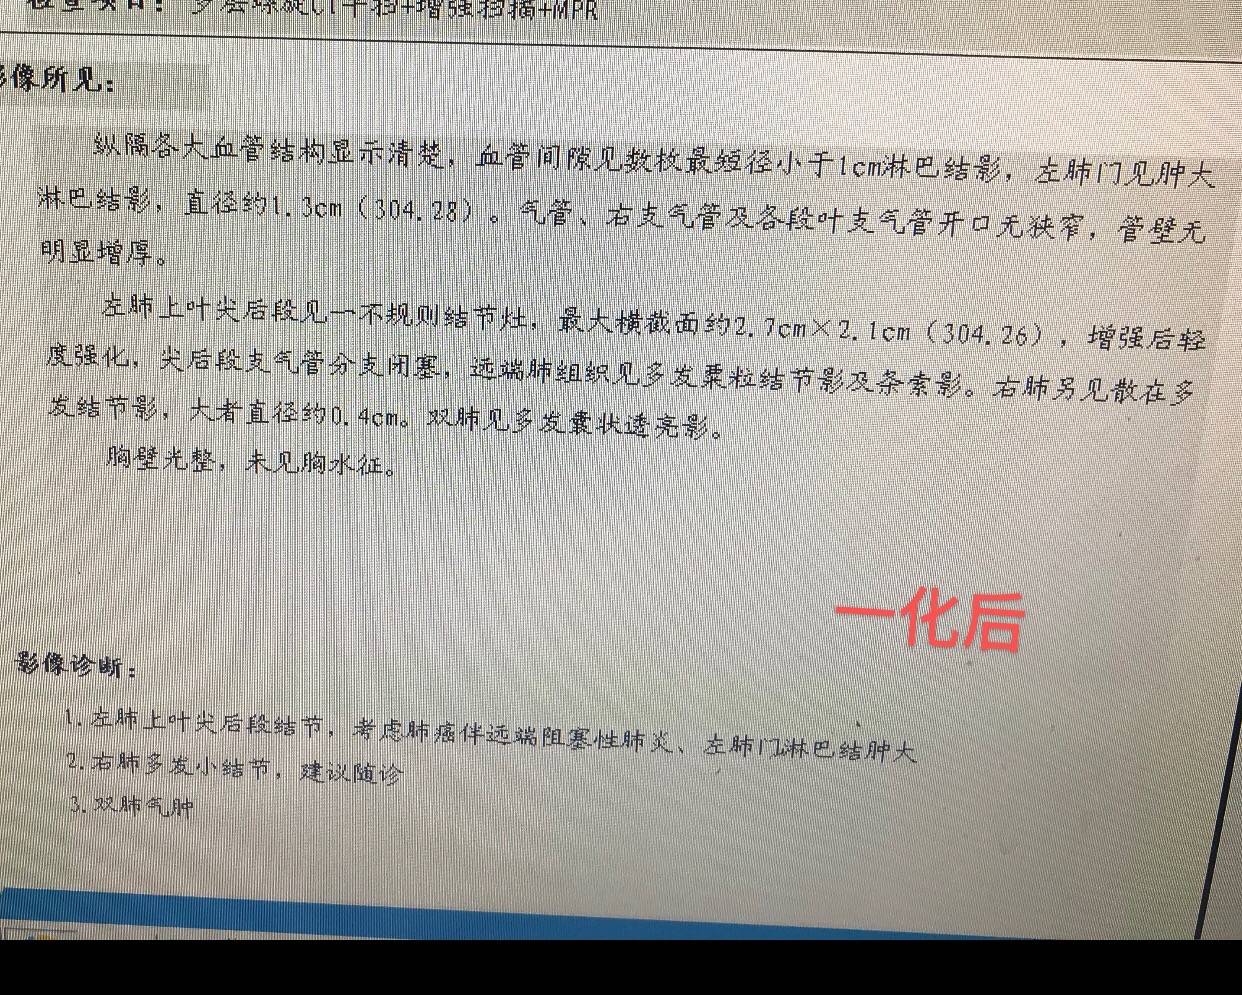

一患者考虑3a或者3b分期的鳞癌,病灶紧贴肺门血管,外科判断暂不能手术,需要新辅助治疗。故前来咨询陈某某医生术前新辅助方案。

患者穿刺小标本PDL1低表达,无敏感用药的基因突变

患者拿不定主意,还是先用白紫加铂做了第一周期术前新辅助化疗,因为比较担心,一周期后,做第二次化疗前就提前复查了一次CT,效果似乎不理想

因为出现心肌酶略增高,三化效果不错,病灶仅剩"少许软组织影"了,故决定抓紧手术。